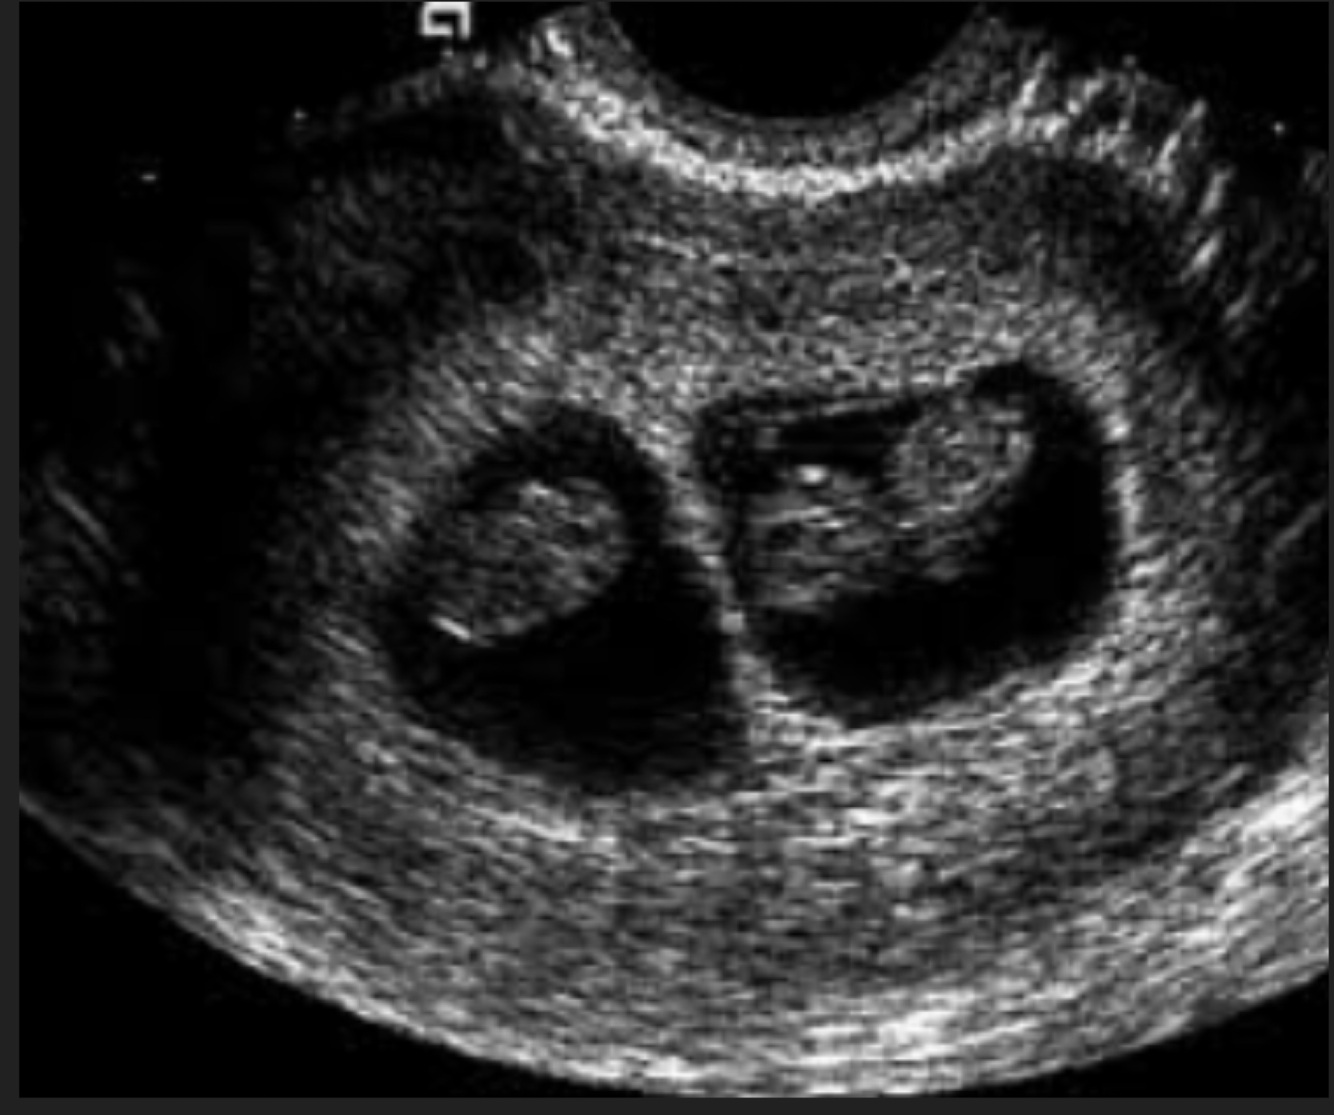

Femenino de 34 años, FUM hace 14 semanas

A

Embarazo múltiple